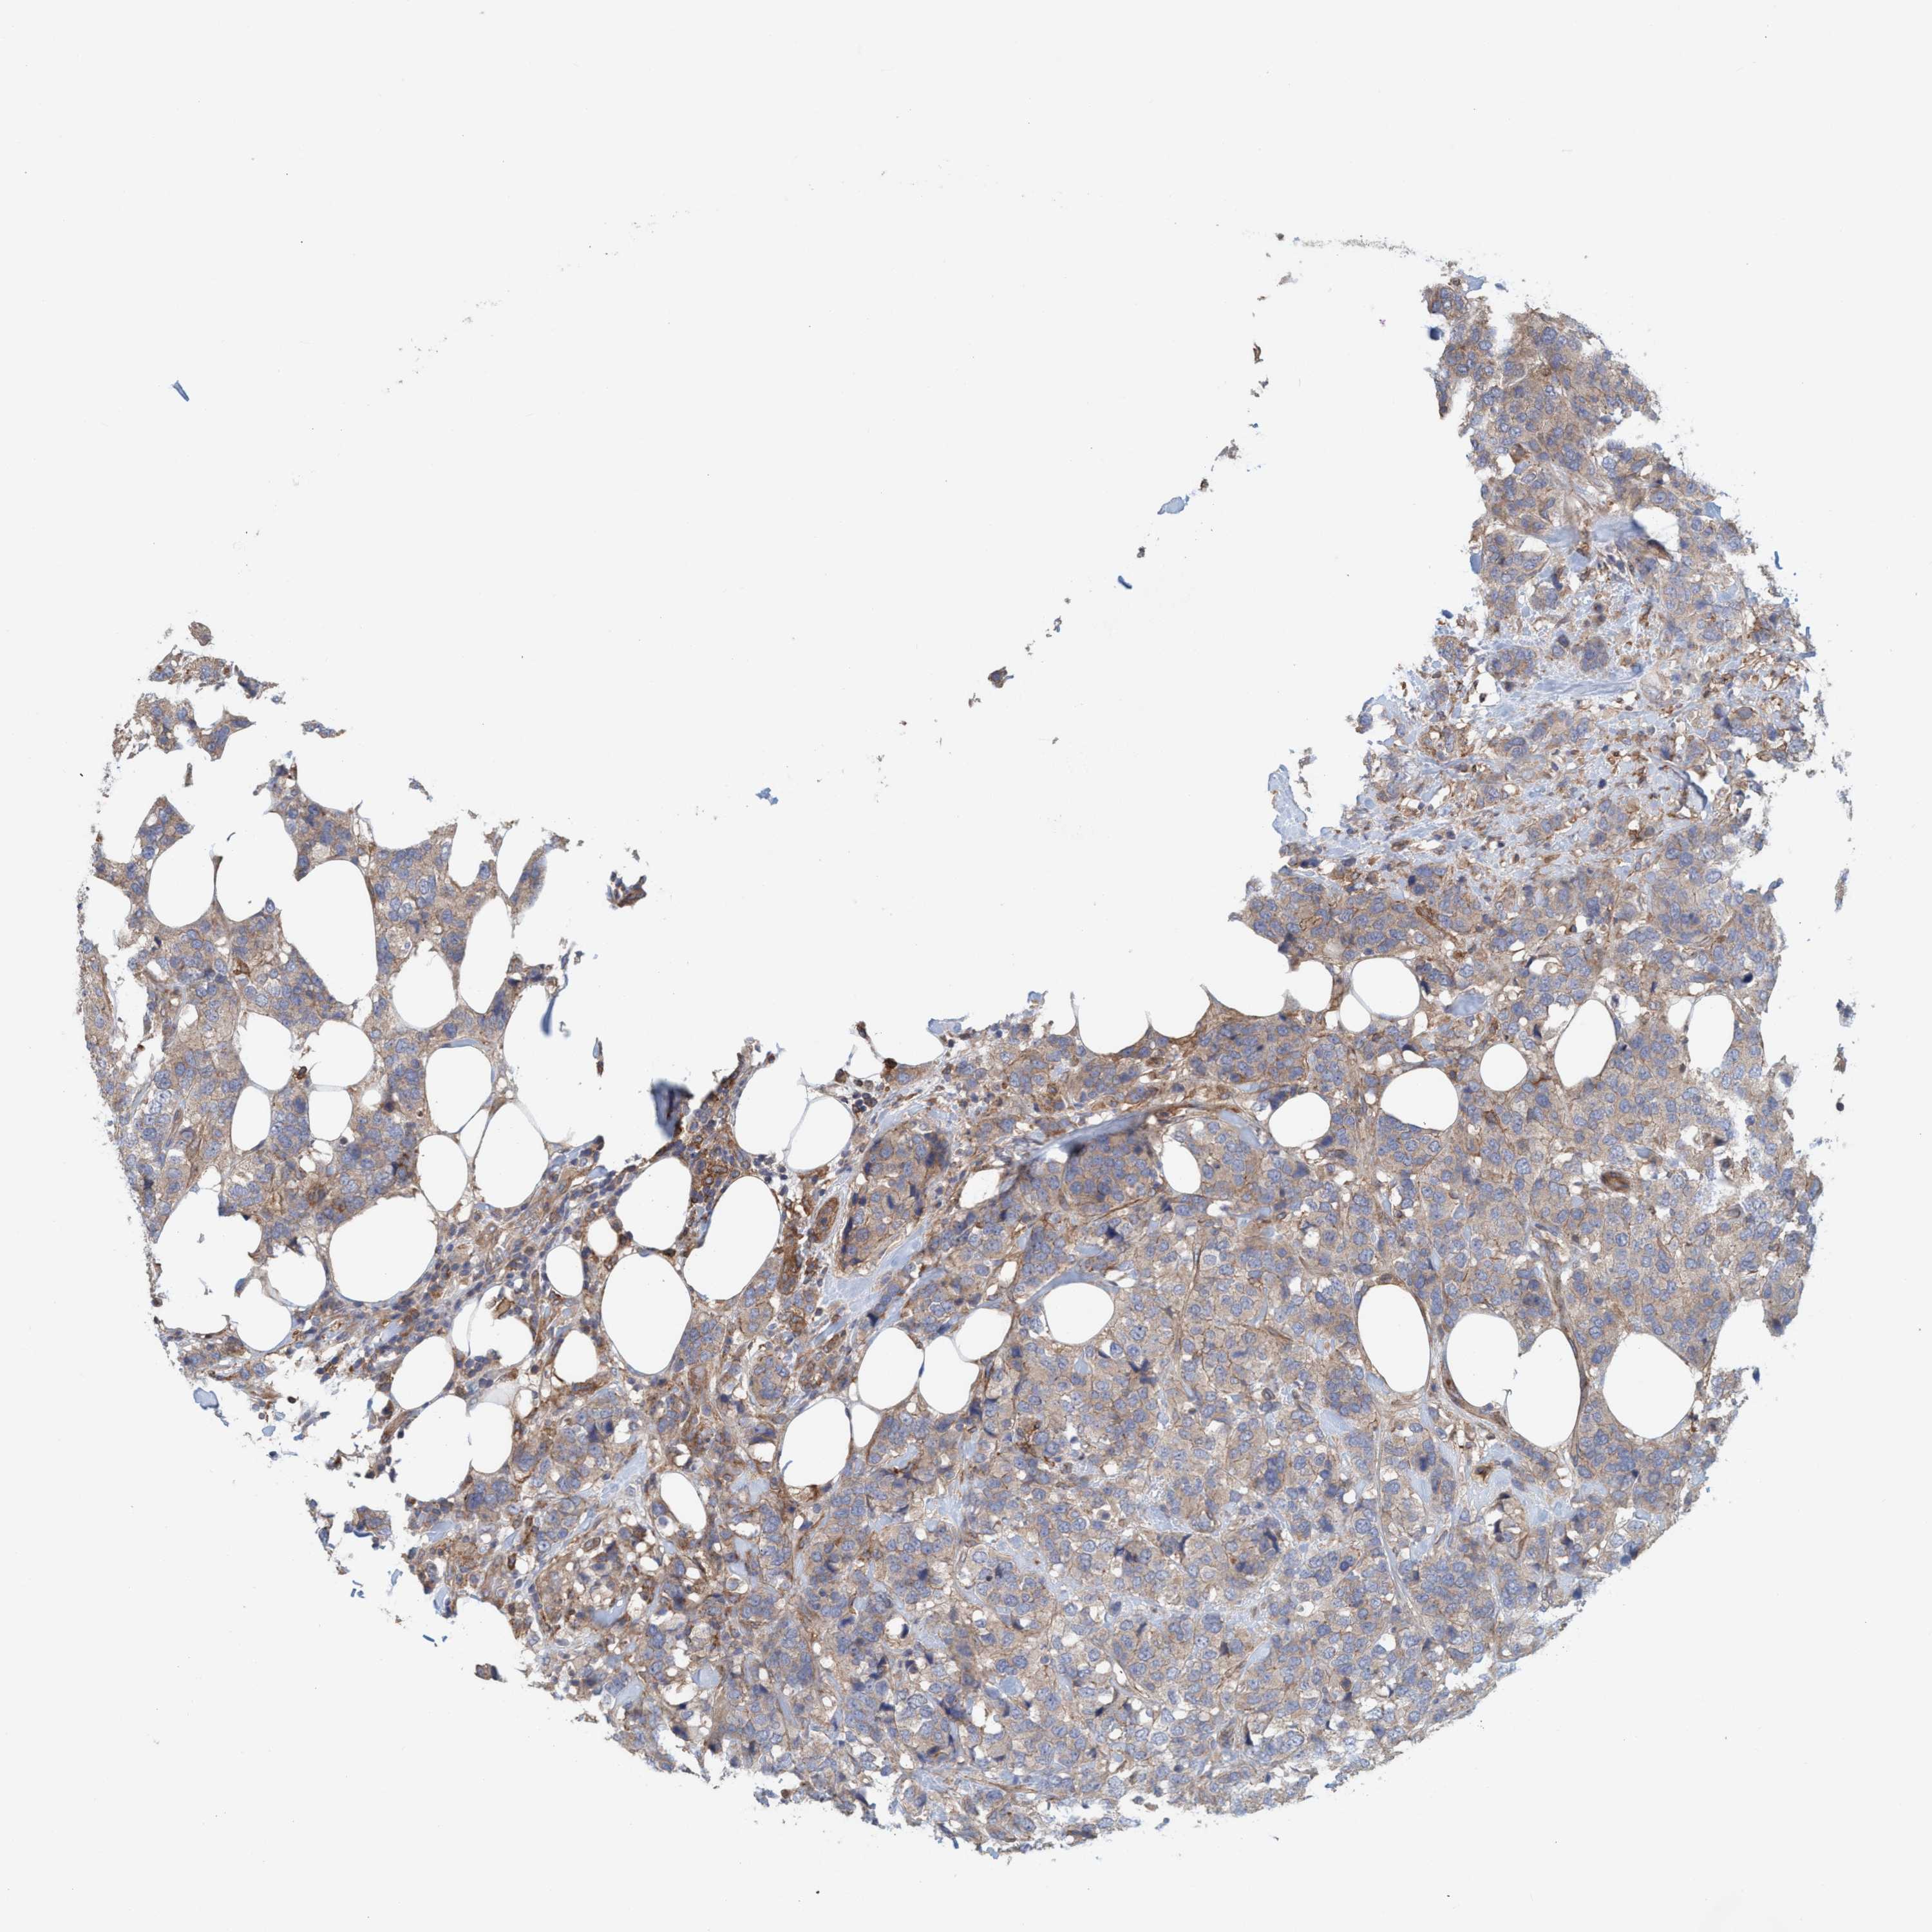

CANCER BREAST CANCER Show tissue menu

BRCA TCGA BRCA VALIDATION PROTEIN EXPRESSION